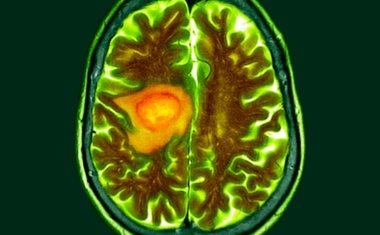

Glioblastome sind bösartige Gehirntumore mit bedrückender Prognose. Die mittlere Überlebenszeit der betroffenen Patienten beträgt bei einer optimalen Standard-Therapie zwölf bis 18 Monate.

Forscher am Deutschen Krebsforschungszentrum (DKFZ) und an der Universitätsmedizin Mannheim (UMM) haben eine vielversprechende zelluläre Immuntherapie zur Behandlung von Glioblastomen entwickelt.

Strahlen- und/oder Chemotherapie nach der Operation – das sind die Behandlungsoptionen bei einem der gefährlichsten Gehirntumore überhaupt, dem Glioblastom. Doch bis heute sind diese Tumoren unheilbar, mit einer mittleren Überlebensdauer von 16 Monaten nach Diagnosestellung.

Glioblastome sind besonders aggressive Hirntumore, die schnell auch in das gesunde Hirngewebe hineinwuchern. Da die Tumore chirurgisch meist nicht vollständig entfernt werden können, ist die Prognose von Glioblastom-Patiententen sehr schlecht.

Die Diagnose Glioblastom geht mit einer schlechten Überlebenschance einher. Der Gehirntumor zählt zu den aggressivsten Krebsarten.

Glioblastome sind bösartige Hirntumore mit schlechter Prognose, da sie in der Regel nicht auf gängige Krebstherapien ansprechen. Ein Grund hierfür ist, dass die Tumorzellen Mechanismen entwickelt haben, um sich der Immunabwehr zu entziehen.

Jedes Jahr erkranken in Deutschland rund 8.000 Menschen an einem Hirntumor. Als besonders aggressiv gilt dabei das Glioblastom, da die Tumorzellen schnell wachsen und in das gesunde Gehirn einwandern.